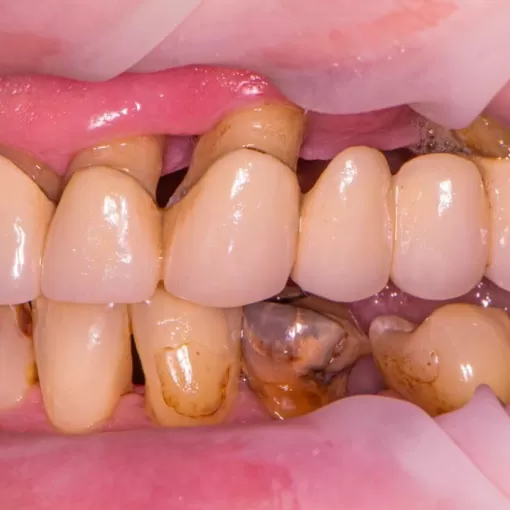

Клинический случай лечения "кисты" зуба 4.7

Стоматолог-терапевт Петрусенко О.А.

Пациент обратился с целью имплантации в области отсутствующего зуба 4.6. Однако после КЛКТ (3Д) исследования был обнаружен воспалительный процесс (киста) в области соседнего зуба 4.7 (рис. 1).